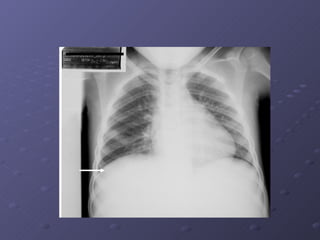

Exames Complementares: Exame Inespecífico: Hemograma completo. Nos casos de forte comprovação: Detecção do Antígeno NS1( FMRP-USP ) RT-PCR para dengue  * Isolamento do vírus. Sorologia Mac-Elisa. Nas complicações: •  Inespecíficos: a) Tipagem sanguínea ; b) Monitorização do hematócrito (2/2 horas); c) Dosagem de eletrólitos séricos e gasometria arterial; d) Contagem de plaquetas, tempo de parcial de tromboplastina e atividade da protrombina; Rx do tórax,Ultrassonografia,dosagem de  albumina, função hepática, função renal e outros exames a depender das complicações.

Complicações: Alterações neurológicas: Tremores, parestesias , hiperestesia cutânea  Diminuição nível de consciência: letargia, agitação, confusão  mental, convulsões  Manifestações psíquicas: Psicose, demência,  amnésia,irritabilidade.  Disfunção cardio-respiratória Insuficiência Hepática Plaquetopenia igual ou inferior a 50.000/mm3  Hemorragia Digestiva  Derrames Cavitários: derrame  pericárdico,pleural ou ascite.

Critérios de Alta Hospitalar A- Ausência de febre por mais de 24 horas B- Melhora visível do quadro clínico. C- Hematócrito normalizado e estável. D- Plaquetas em elevação > 50.000/mm³. E- Estabilização hemodinâmica por 24 horas, F- Derrames cavitários em regressão e sem repercussão clínica, quando presentes.